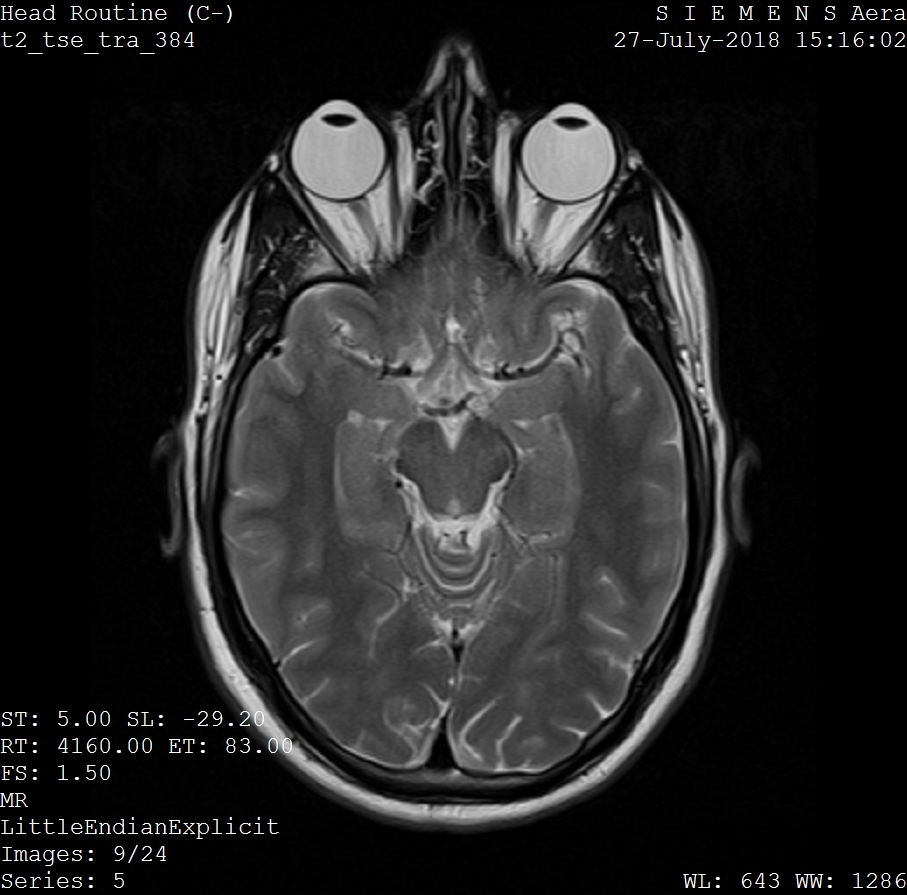

Brain and orbit MRI scans are specialized imaging procedures that use magnetic fields and radio waves to create detailed pictures of the brain, eye sockets, and surrounding structures without using radiation.

You already know what the brain is, but the term βorbitalβ is less common. The orbitals are the sockets in the skull that hold the eyes. They also contain the nerves, blood vessels, muscles, and other tissues that allow the eyes to function. The brain and orbitals are close together, making it easier to scan both simultaneously compared to more distant body sites. Healthcare providers can choose to image different areas of the brain and the orbitals depending on the disease they are examining.

These scans help assess, diagnose, and monitor a variety of health issues related to the eyes and neurological tissue. Radiologists use different settings on MRI machines to scan for abnormalities that include but are not limited to, cancers such as retinoblastoma and glioma, multiple sclerosis, stroke, microbial infections, retinal detachment, endophthalmitis (inflammation of the inner eye coating), neuropathies, and posttraumatic hemorrhagic cysts.

MRI helps identify conditions affecting the eyes and surrounding structures, such as orbital tumors or optic nerve issues. For example, retinoblastomas grow inside the vitreous chamber (the largest chamber of the eye), and MRI scans can identify retinoblastomas because they are denser than the fluid within the vitreous chamber. Optic nerve gliomas are clearly visible on MRI as enlargements of the optic nerve and are easily comparable to the unaffected nerve on the other side.